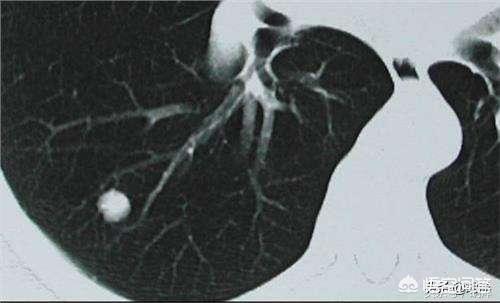

Les nodules pulmonaires sont classés en différents types en fonction de leur densité. Les nodules de densité plus élevée, qui apparaissent comme des points blancs sur le scanner thoracique, sont appelés nodules solides, tandis que les nodules en verre dépoli sont plus légers et ressemblent à de la vapeur d'eau sur le verre. Les nodules en verre dépoli, en particulier les nodules en verre dépoli pur, ont tendance à être plus malins.

Pour la définition du nodule pulmonaire, la directive médicale chinoise indique : L'imagerie (scanner thoracique) montre une ombre pulmonaire solide ou sous-solide focale, arrondie, de densité accrue, d'un diamètre ≤3 cm, qui peut être isolée ou multiple, et qui n'est pas accompagnée d'atélectasie pulmonaire, d'hypertrophie des ganglions lymphatiques hilaires et d'épanchement pleural.

D'une manière générale, toute ombre de densité accrue dans les poumons d'un diamètre inférieur à 3 cm est appelée nodule pulmonaire. Le degré de risque n'est pas seulement lié à la taille, mais doit également être déterminé en fonction de la morphologie, de la densité et de la vitesse de multiplication du nodule.

Nous connaissons cette idée de diagnostic de la maladie, puis nous revenons à la tête pour parler des nodules pulmonaires. Les nodules pulmonaires sont des lésions rondes ou irrégulières d'un diamètre inférieur ou égal à 3 cm dans les poumons, qui apparaissent à l'imagerie comme des ombres de densité accrue, qui peuvent être homogènes ou inhomogènes, qui peuvent être uniques ou multiples, et qui peuvent avoir des limites claires ou floues.